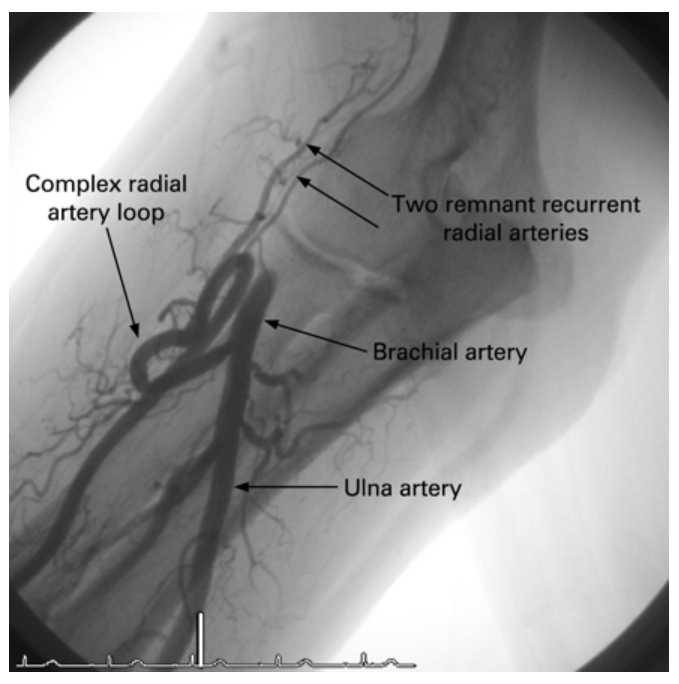

圖5 復(fù)雜的橈動(dòng)脈-尺動(dòng)脈大環(huán),注意兩條橈動(dòng)脈遠(yuǎn)端分支從環(huán)的頂端往手臂上端反向形成(這個(gè)時(shí)候一般就換個(gè)手或者做腿吧~)

到了University at Buffalo的教授們手里,對(duì)于無法常規(guī)技術(shù)通過的橈動(dòng)脈變異,則又是另一種玩法。2019年,Rimal Dossani教授等發(fā)表在BMJ上的一個(gè)75歲男性案例中,他們使用帶硬導(dǎo)絲的微導(dǎo)管系統(tǒng)在路圖引導(dǎo)下,成功將成環(huán)的橈動(dòng)脈拉直后,進(jìn)入顱內(nèi),從而順利治療該患者的硬膜下血腫。